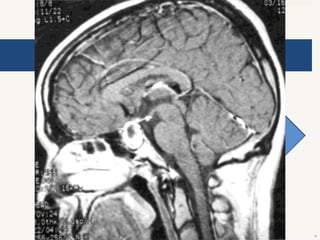

Síndrome de silla turca vacía

 Congénita o adquirida después de cirugía.